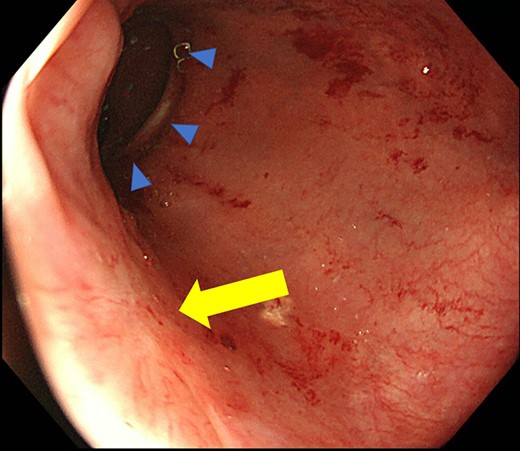

Case 1 was a 71-year-old man with a BMI of 29.7 kg/m2. Laparoscopic low anterior resection (LAR) and ileostomy was performed for rectal cancer in 2017 years. Postoperative fever and lower abdominal pain were noted, and colonoscopy was performed, and anastomotic leakage was noted with a correction of about 1/2 around the 6 o’clock direction of the anastomotic region, and fistula and formation of a large abscess cavity. After identification (Fig. 1), a tube was inserted for drainage and conservative treatment was performed. The patient was discharged on POD 46. Four months after the operation, marked improvement in the abscess cavity was noted but still remained (Fig. 2a and b). Anastomotic leakage was almost improved by colonoscopy at 17 months after surgery, but at the preference of the patient we performed colostomy 22 months after surgery (Fig. 3). It took a long time to improve intestinal movement of the colon because the large intestinal tract had not been used for a long time, and conservative treatment was performed using a nasogastric tube for paralytic ileus. Diet was initiated 7 days after surgery, and the patient was discharged from the hospital 14 days after surgery. The Wexner score [2] was 19 points one month after closure, 17 points 3 months after the operation and 16 points after 6 months after the operation, and severe anal dysfunction was observed, but gradually improved.

(a) Colonoscopy shows a fistula (arrow). (b) Enema examination shows a cavity (arrow) leading from the fistula.